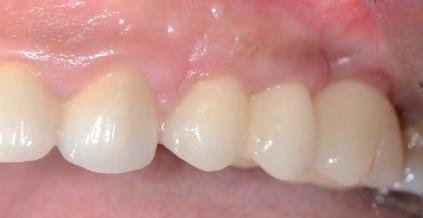

Situation avant la prise d’empreinte en sept. 2009

• Etude de la prothèse sur implants (provisoire, immédiate et définitive).

Situation pré-opératoire 09/2018 09/2018

Contrôle à 10 ans en septembre 2018.